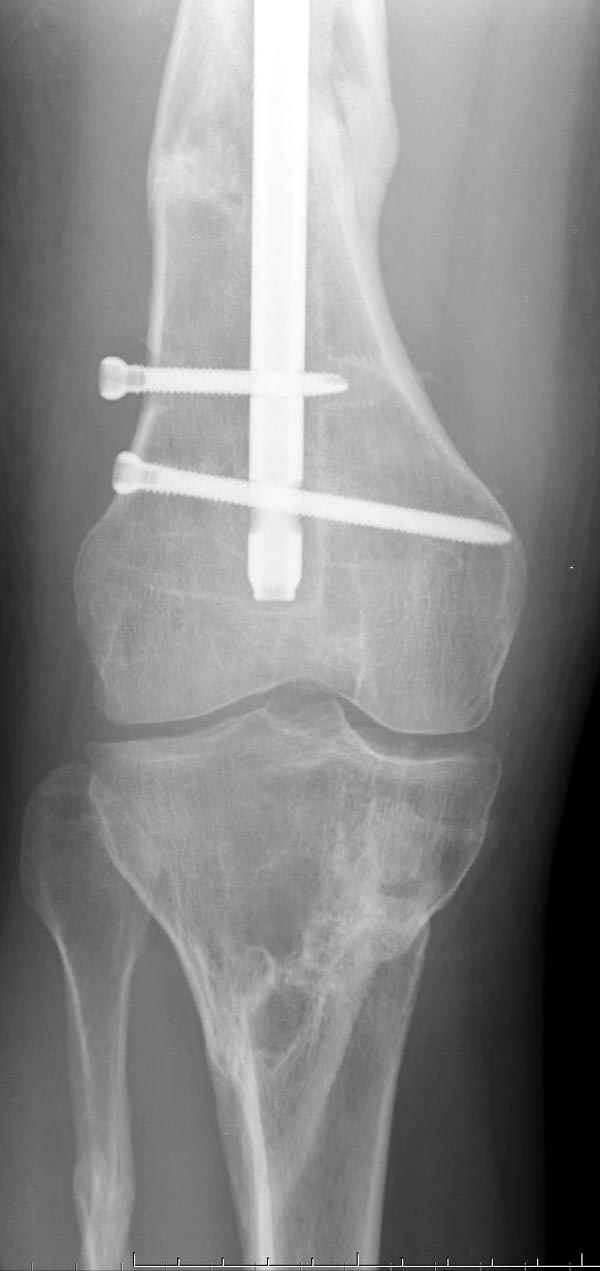

Мы не дождались “Happy End”, у больного IQ в пределах 70%, через 6 месяцев вернулся после небольшой травмы, споткнувшись получил перелом

того же бедра (рис №7).

На следующий день произвели интрамедуллярный остеосинтез: этапы во время операции (рис №8, №9)

и последующих снимках (рис №10, 11, 12, 13) перелом сростается и передвигается с полной нагрузкой.

При обзоре причин перелома, на снимке №2 обнаружили, что один из стержней аппарата наружной фиксации проходил только через передний кортекальный слой, что создало стрессовую зону на бедре и в результате перелом из-за незначительной травмы.